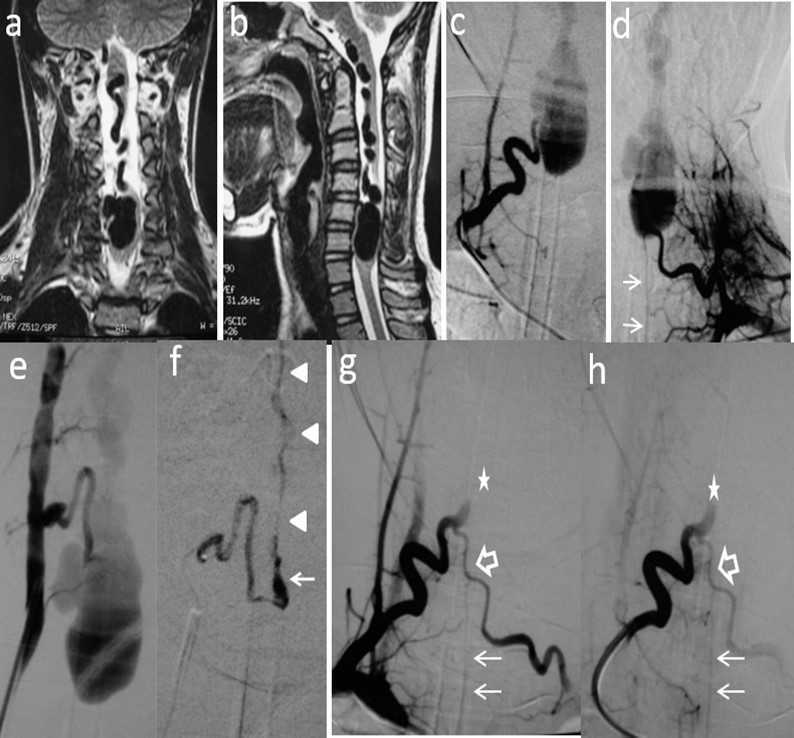

Figure 2.Case # 2: a) Coronal and b) sagittal T2W MRI shows large venous varix compressing ventrally the cervical cord at C5-C6 levels causing moderate central hyperintensity above, and mild below the cervical cord. Ascending convoluting draining veins reach the brainstem. c) d) and e) Angiograms showing right and left arteries of the cervical enlargement as well as a PSA of the right vertebral artery. All of them converge and shunt the varix at the same fistulous point. The ASA branches off the left artery of the cervical enlargement (thin arrows). f) DSA shows the right PSA feeder catheterized proximally. An injection of 30% n-bca in lipiodol was performed reaching the fistulous point (arrow). A thin layer of glue cast is seen in the lateral wall of the ascending vein (arrowheads) g) and h) Post-embolization right ascending cervical artery angiogram showing an arterial blockade at the entry of the fistulous point (star) preserving its anastomosis with the contralateral artery (open arrow). Notice that by reflux, the left artery of the cervical enlargement fills the ASA (thin arrows). Four hours later, the patient suddenly developed quadriplegia probably due to venous and/or ASA thrombosis. Patient lost to follow-up after 2 months.

Two out of 4 patients were diagnosed and studied preoperatively with both spinal MRI and CT scans, 1 patient with MRI and the other patient with CT/CT Angiography with 3D reconstruction. Large and tortuous flow voids with large to giant venous pouches or pseudoaneurysms (3 of our cases - type c) causing compression of the spinal cord were found lying ventrally and, in another one, posterolaterally to the spinal cord. Hyperintensity in T2W sequences in the spinal cord was noted in all of them. There were no cases where a hemorrhage was exhibited. The angiographic studies confirmed the 4 large or giant pouches at the draining vein fed by ASA and or PSA and ascending (2 cases), descending (1 case) or metameric (1 case) venous drainage. The blood flow was moderate in 1 case and very fast in the other 3 patients (see Table 2 and Figure 1, Figure 2, Figure 3, Figure 4).

We used transarterial approach and a single session achieving complete obliteration of the fistulae while preserving the normal vasculature, mainly the ASA, in all of our 4 cases using either different concentrations of n-bca alone tailored to the blood flow velocity (cases 1,2 and 3), or a combination of coils and onyx 18 (case 4). In this last case, the high flow fistula and the presence of a giant pseudoaneurysm at the venous varix compressing the spinal cord prompted us to deploy coils in the sac and in the draining vein to slow down the blood flow and decrease the chance of distal embolism. To date, we do not have Onyx of higher concentration than Onyx18 available in our country. In high flow macrofistulae, our strategy to slow down the flow to allow casting of the polymerizing embolic mixture in the fistulous site avoiding distal embolism includes lowering mean arterial pressure down to 60-70 mm Hg pharmacologically, by embolizing with concentrations of 66% of n-bca in lipiodol, as well as the placement of detachable coils in the event of very high flow with pseudoaneurysms at or very close to the fistulous site as a first step, to trap the liquid embolic material injected as second step (see Figure 1, Figure 2, Figure 3, Figure 4).